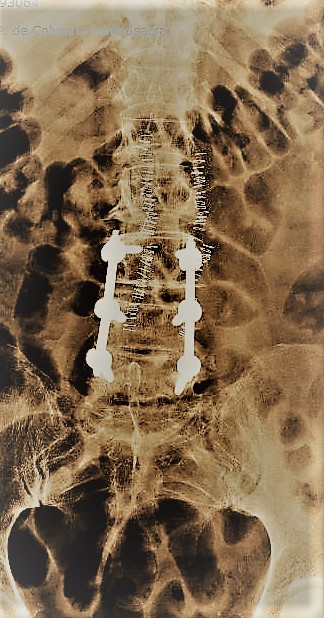

- Estabilizacion vertebral percutánea: Es el procedimiento empleado para tratar los casos que precisan fijar dos o más vértebras debido a la presencia de inestabilidad o fracturas. Gracias al empleo de imagen intraoperatoria y a los sistemas de fijación de alta precisión es posible llevar a cabo esta técnica de forma mínimanente invasiva mediante pequeñas incisiones de apenas 2 cm a través de las cuales se introducen tornillos al pedículo de la vértebra así como barras laterales. El respeto por la musculatura paraespinal, clave para el resultado final, es por tanto máximo gracias a esta técnica. La ejecución de la misma gracias al aprovechamiento de aspectos como la colocación bicortical de los implantes y las técnicas de reduccion percutánea de la deformidad permiten un restablecimiento de la anatomía en una amplia proporción de casos con un riesgo mínimo.